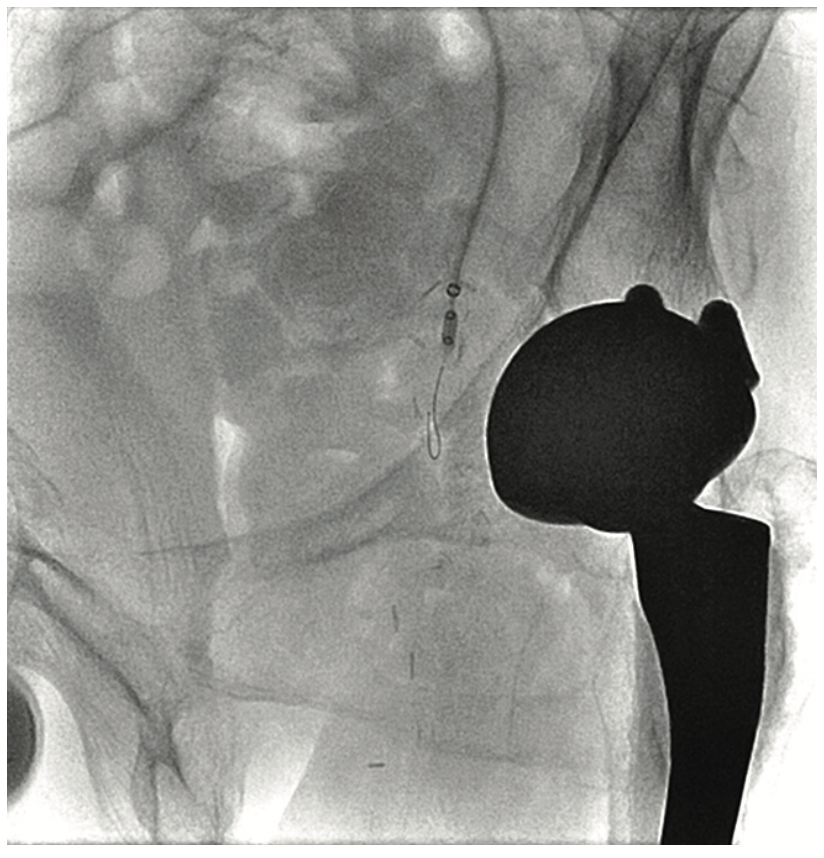

A 63-year-old male smoker presented with critical limb ischemia of his left foot. Four years prior, the patient underwent right fem-pop bypass after failed intervention on his right leg. He ended up losing the fifth digit on his right foot. Three years prior to his visit, he underwent a fem-pop bypass procedure on his left leg for severe claudication after failed intervention. One year later, he underwent a redo fem-pop on his left leg with a cadaveric vein. Twelve months prior to the visit, a self-expanding stent was placed in that fem-pop graft because of continued foot ischemia. Seven months prior to his visit, his symptoms re-occurred, and the patient was told nothing could be done after an angiogram showed the vessel was occluded. The patient suffered from polyneuropathy and was unable to walk, but did not want amputation. The patient was on cilastazol and coumadin, and had type II diabetes mellitus. His exam revealed a cool and red left foot, but no ulcers. Capillary filling was adequate. The right dorsalis pedis was normal, and there was no popliteal pulse on either side and no left pedal pulses. A contralateral approach was utilized and revealed the graft was occluded on the left side (Figure 1). The patient likely had thrombus in the graft, and we felt that a laser would be appropriate, used either in the traditional manner or with the step-by-step method. Whenever the step-by-step method is utilized, we use the CrossLock LP device (Radius Medical) for centering (Figure 2). The CrossLock LP is usually utilized for infrapopliteal lesions, but in this case, the 3 mm elastomeric balloon would fit well into the nub of the bypass graft. We immediately subtended the bypass graft all the way down and then were able to access the infrapopliteal vessels (Figures 3-4). We performed .9 mm laser (Spectranetics) in the graft and balloon angioplasty (Figure 5). Two Xience stents (Abbott Vascular) were placed, a 4.0 cm and 3.5 cm, at the anastomosis site, and because of residual stenosis at the popliteal, we placed a 5.5 cm Supera stent (Abbott Vascular). Due to multiple failures of the graft, the graft was covered with a 6.0 mm x 250 mm Gore Viabahn stent graft (W.L. Gore & Associates). At the end of the procedure, we were able to achieve brisk 2-vessel runoff (Figures 6-7). Fluoroscopic time was long at 73 minutes and the contrast utilization was 236 mL.